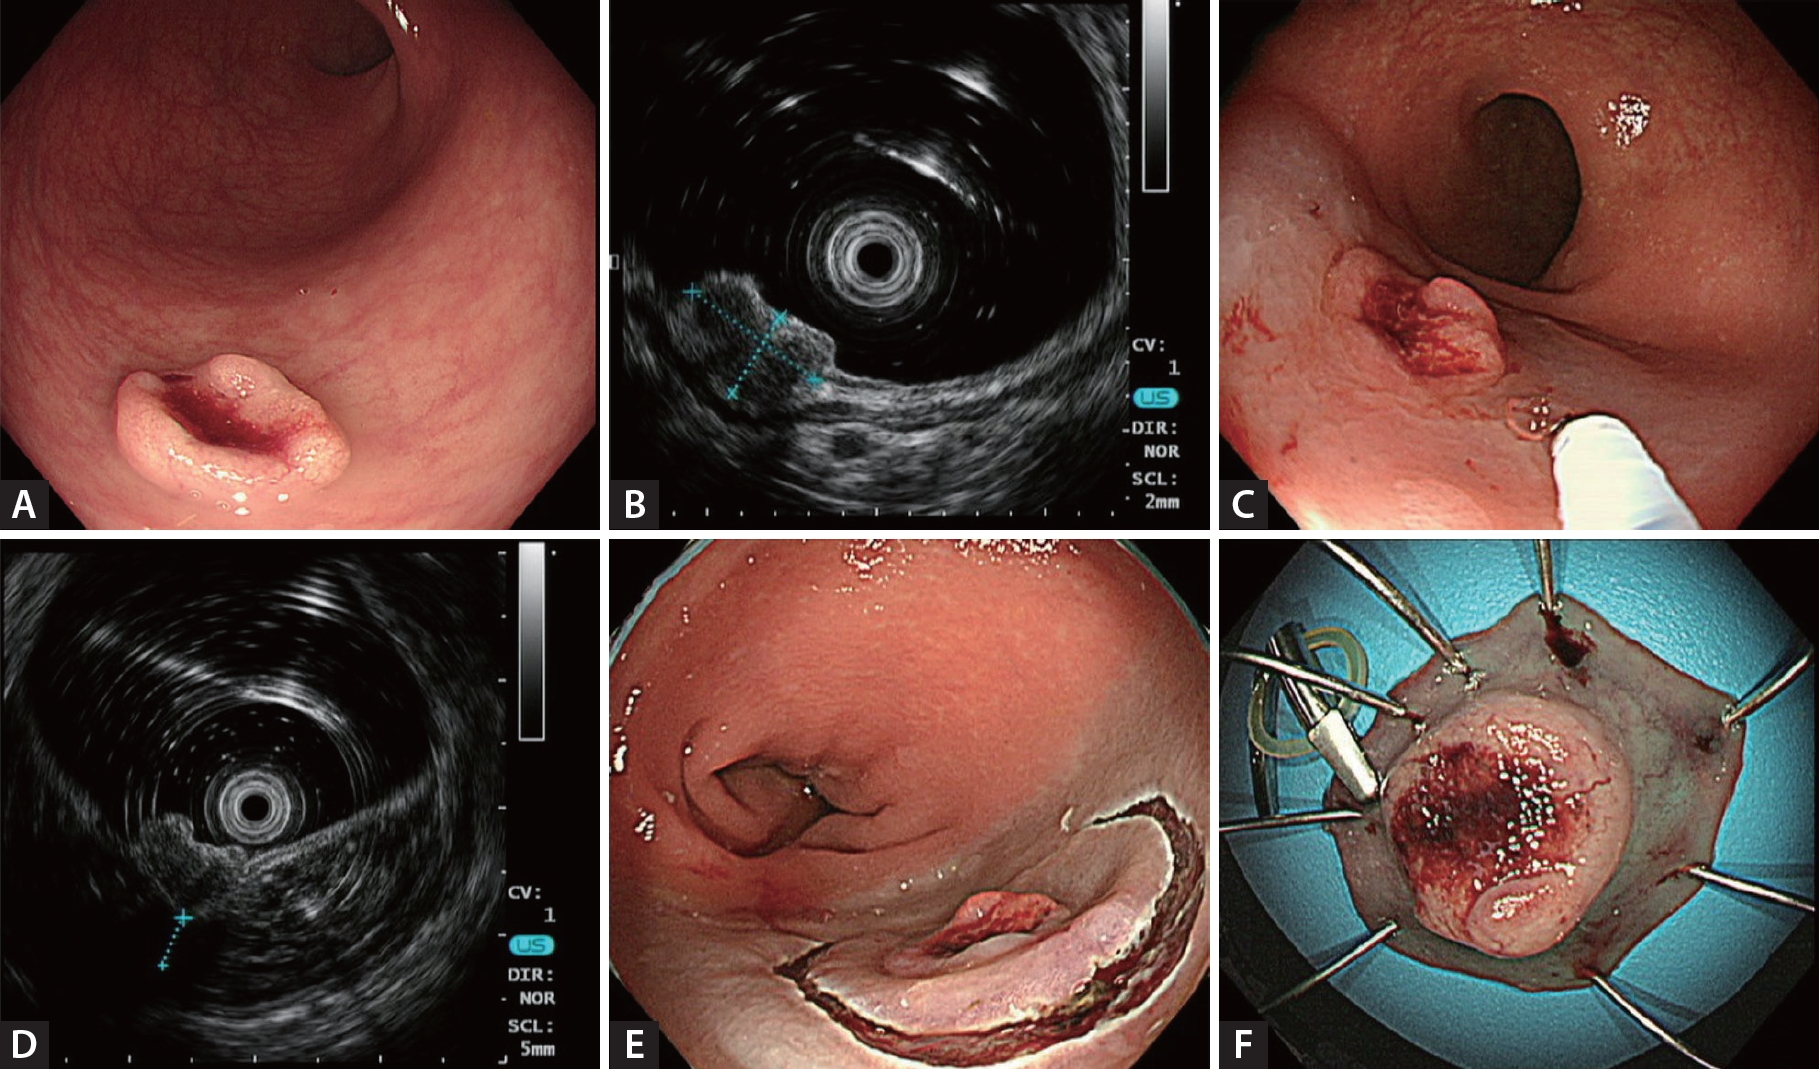

Example mini-probe endoscopic ultrasound image of a colorectal subepithelial lesion. (A) Subepithelial lesion with central ulceration. (B) Mini-probe endoscopic ultrasound image showing a 9.0 × 5.3 mm hypoechoic nodule with a slightly disrupted interface between the third and fourth layers. (C, D) Distance between the third and fourth layers of 4.7 mm after submucosal saline injection. (E, F) Lesion removed by endoscopic submucosal dissection with a final histology of 13 mm, grade 2 rectal neuroendocrine tumor and clear resection margins.